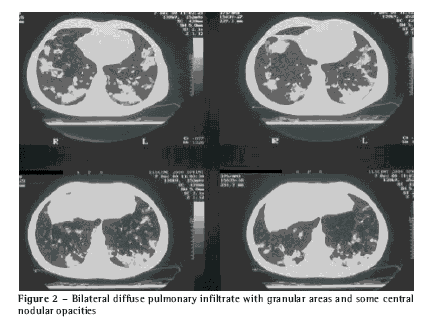

Imaging: bilateral diffuse micronodular infiltrate, with granular areas and some central nodular opacities, on the computed tomography scan of the chest. There was no evidence of lymph node enlargement in the mediastinum (Figure 2).

Mycological evaluation: mycological blood culture with immunodiffusion negative for H. capsulatum; histopathology of lingula sample (obtained through lung biopsy) stained with hematoxylin and eosin showing tuberculoid granuloma with caseous necrosis and fibrosis in the lung parenchyma; the Grocott-Gomori methenamine silver staining revealing numerous small, round or oval budding yeast-like cells suggestive of H. capsulatum; culture was negative.

This unusual radiological pattern is suggestive of massive inoculation in a non-endemic area, causing a severe inflammatory reaction(1). Culture is positive in only 15% of cases of the self-limited forms(4).